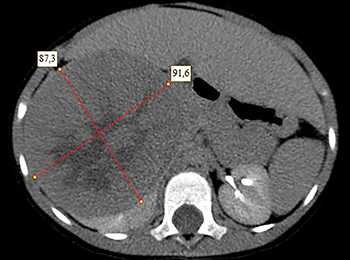

- Компьютерная томография органов брюшной полости и забрюшинного пространства с оральным и внутривенным контрастированием (см. рис. 1).

Рисунок 1. КТ брюшной полости ребенка с большой нефробластомой с метастазами в печень.

Клинически: при пальпации опухоль в проекции правой почки до 12 см в диаметре. Общеклинические исследования в пределах возрастной нормы. При КТ органов брюшной и грудной полости: КТ-картина объемного образования правой почки без признаков интрапульмональных метастазов (см. рис. 2). УЗИ брюшной полости: в проекции правой почки солидно-кистозное образование 101ґ114ґ99 мм, объемом 500 мл, васкуляризация активная, интактная часть почки 57ґ12ґ40 мм. Объемное образование правой почки — опухоль Вильмса. Предварительный диагноз: опухоль Вильмса правой почки, 2-я стадия.

Ребенку проведена предоперационная химиотерапия. На 5-й неделе лечения КТ-контроль показал уменьшение опухоли в размерах до 90ґ80ґ100 мм (см. рис. 3).